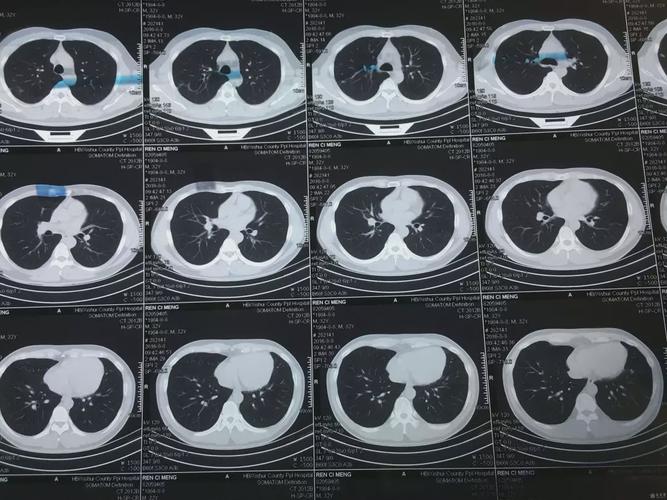

有没有懂的看ct胸片的,肺部咋样,谢谢了

健康肺部ct图片

正常人的肺部ct图片

正常肺部ct图